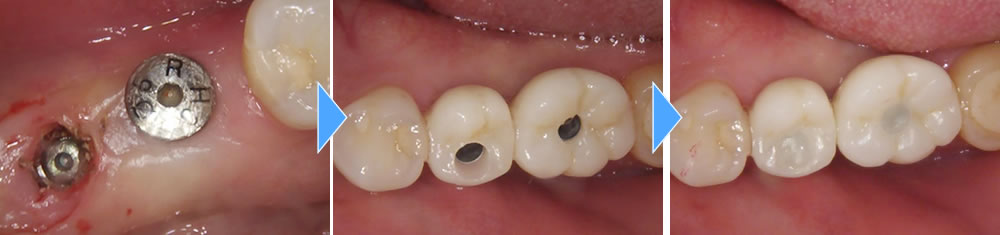

上部構造の装着・治療完了

インプラントと顎骨の結合期間を経て、上部構造を製作しました。その後、完成した上部構造をインプラントに装着し、咬み合わせを調整して治療完了です。

インプラント埋入後は噛んだ時の痛みもなくなり、普通の歯と同じようにしっかりと固いものも噛むことができ、大変満足していただいております。